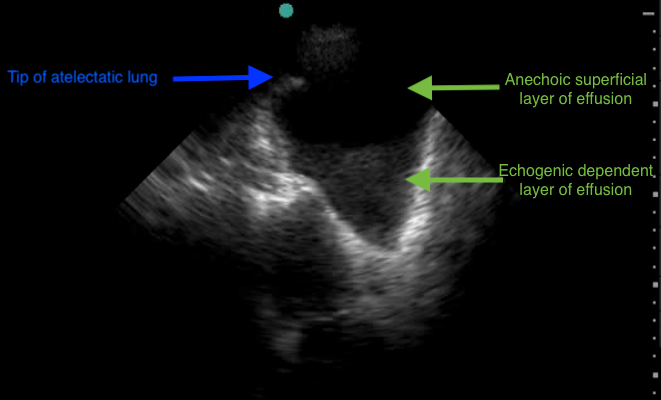

Ultrasonography of the right chest (Video 1) shows a pleural effusion as determined by the presence of a relatively hypoechoic space, bound by the anatomic boundaries of chest wall, diaphragm, and lung, and with the dynamic sign of atelectatic lung tip “swimming” in the fluid. The effusion itself has two different echodensities within it (Figure 2). The more dependent area has greater echogenicity than the more superficial anechoic layer. This occurs in highly cellular effusions, where the cellular debris settles down in the gravitationally dependent area, leaving a relatively clear supernatant. This concept, where cellular material within liquid precipitates out and settles in the dependent area, is the same by which hematocrit is measured in peripheral blood, hence the name hematocrit sign. While hematocrit sign can be present in hemothorax, it is not pathognomonic of blood in the pleural space, despite the nomenclature. It can be seen in any effusion that is highly cellular. Of the options provided, malignant pleural effusion is most likely to exhibit hematocrit sign.

The presence of hematocrit sign also indicates that the effusion is not a transudate, has cellular material and debris in it, and should be consistent with an exudate if sampled and tested. Occasionally, if the fluid sample consists of the supernatant only, it can test as a transudate; therefore, with this phenomenon in mind, if clinically indicated, repeating diagnostic thoracentesis can yield more accurate results.